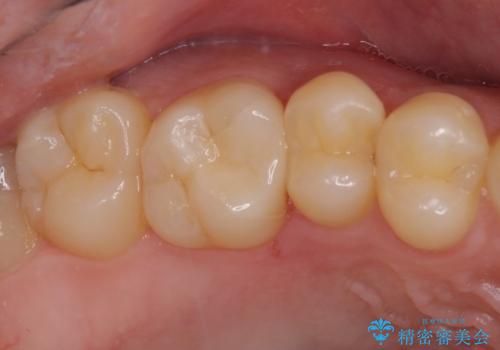

フロスが引っかかる セラミックインレーによるむし歯治療

- ウェブサイトの症例(https://seimitsushinbi.jp/case/9473/)を見て、同じようにフロスが引っかかるとのことで来院された患者様です。

虫歯を除去した後、セラミックインレーにて修復治療を行うこととしました。

セラミックインレー装着後はフロスの引っかかるストレスから解放され、患者様には大変満足していただきました。